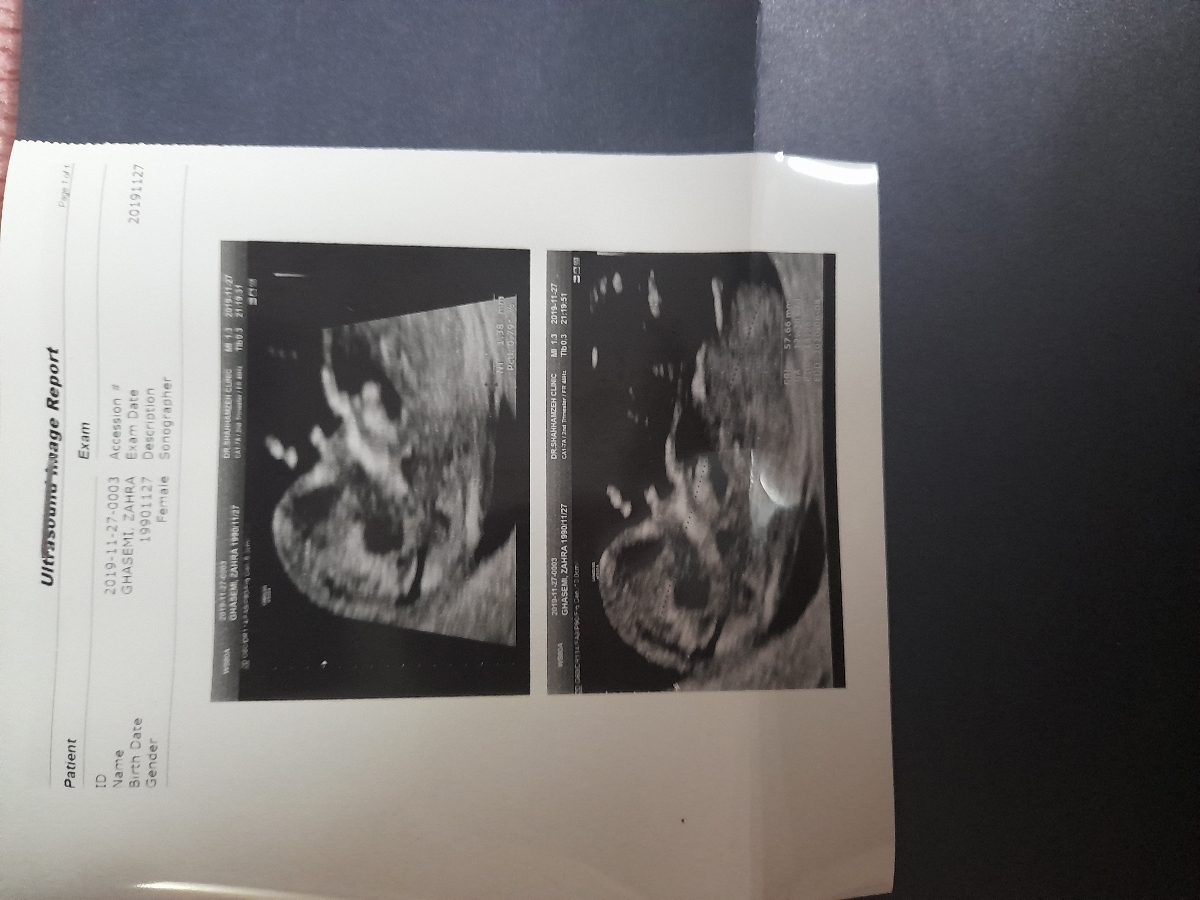

سلام خانما و اوما عزیز لطفا سونو غربالگری ببینین خوبه

تاریخ سونوت زده 2019 بعدم حق داره نوشته female

جنسیت خودشو زده نه بچه

اون مشخصات مادره

ان تی مشخص نیست ان شااله سالمه و به سلامتی بغلش میکنی

اینکه بچه ها میگن زده femaleمنظورشون روی عکس سونو هست که مشخصات خودته و ربطی به جنسیت جنین نداره

چیزی از جنسیت بچه توی سونو نیست

پزشک اوما

سلام سونو خوبه اما جفت کامل سرراهی هست و باید استراحت کنید و نزدیکی نداشته باشید ،